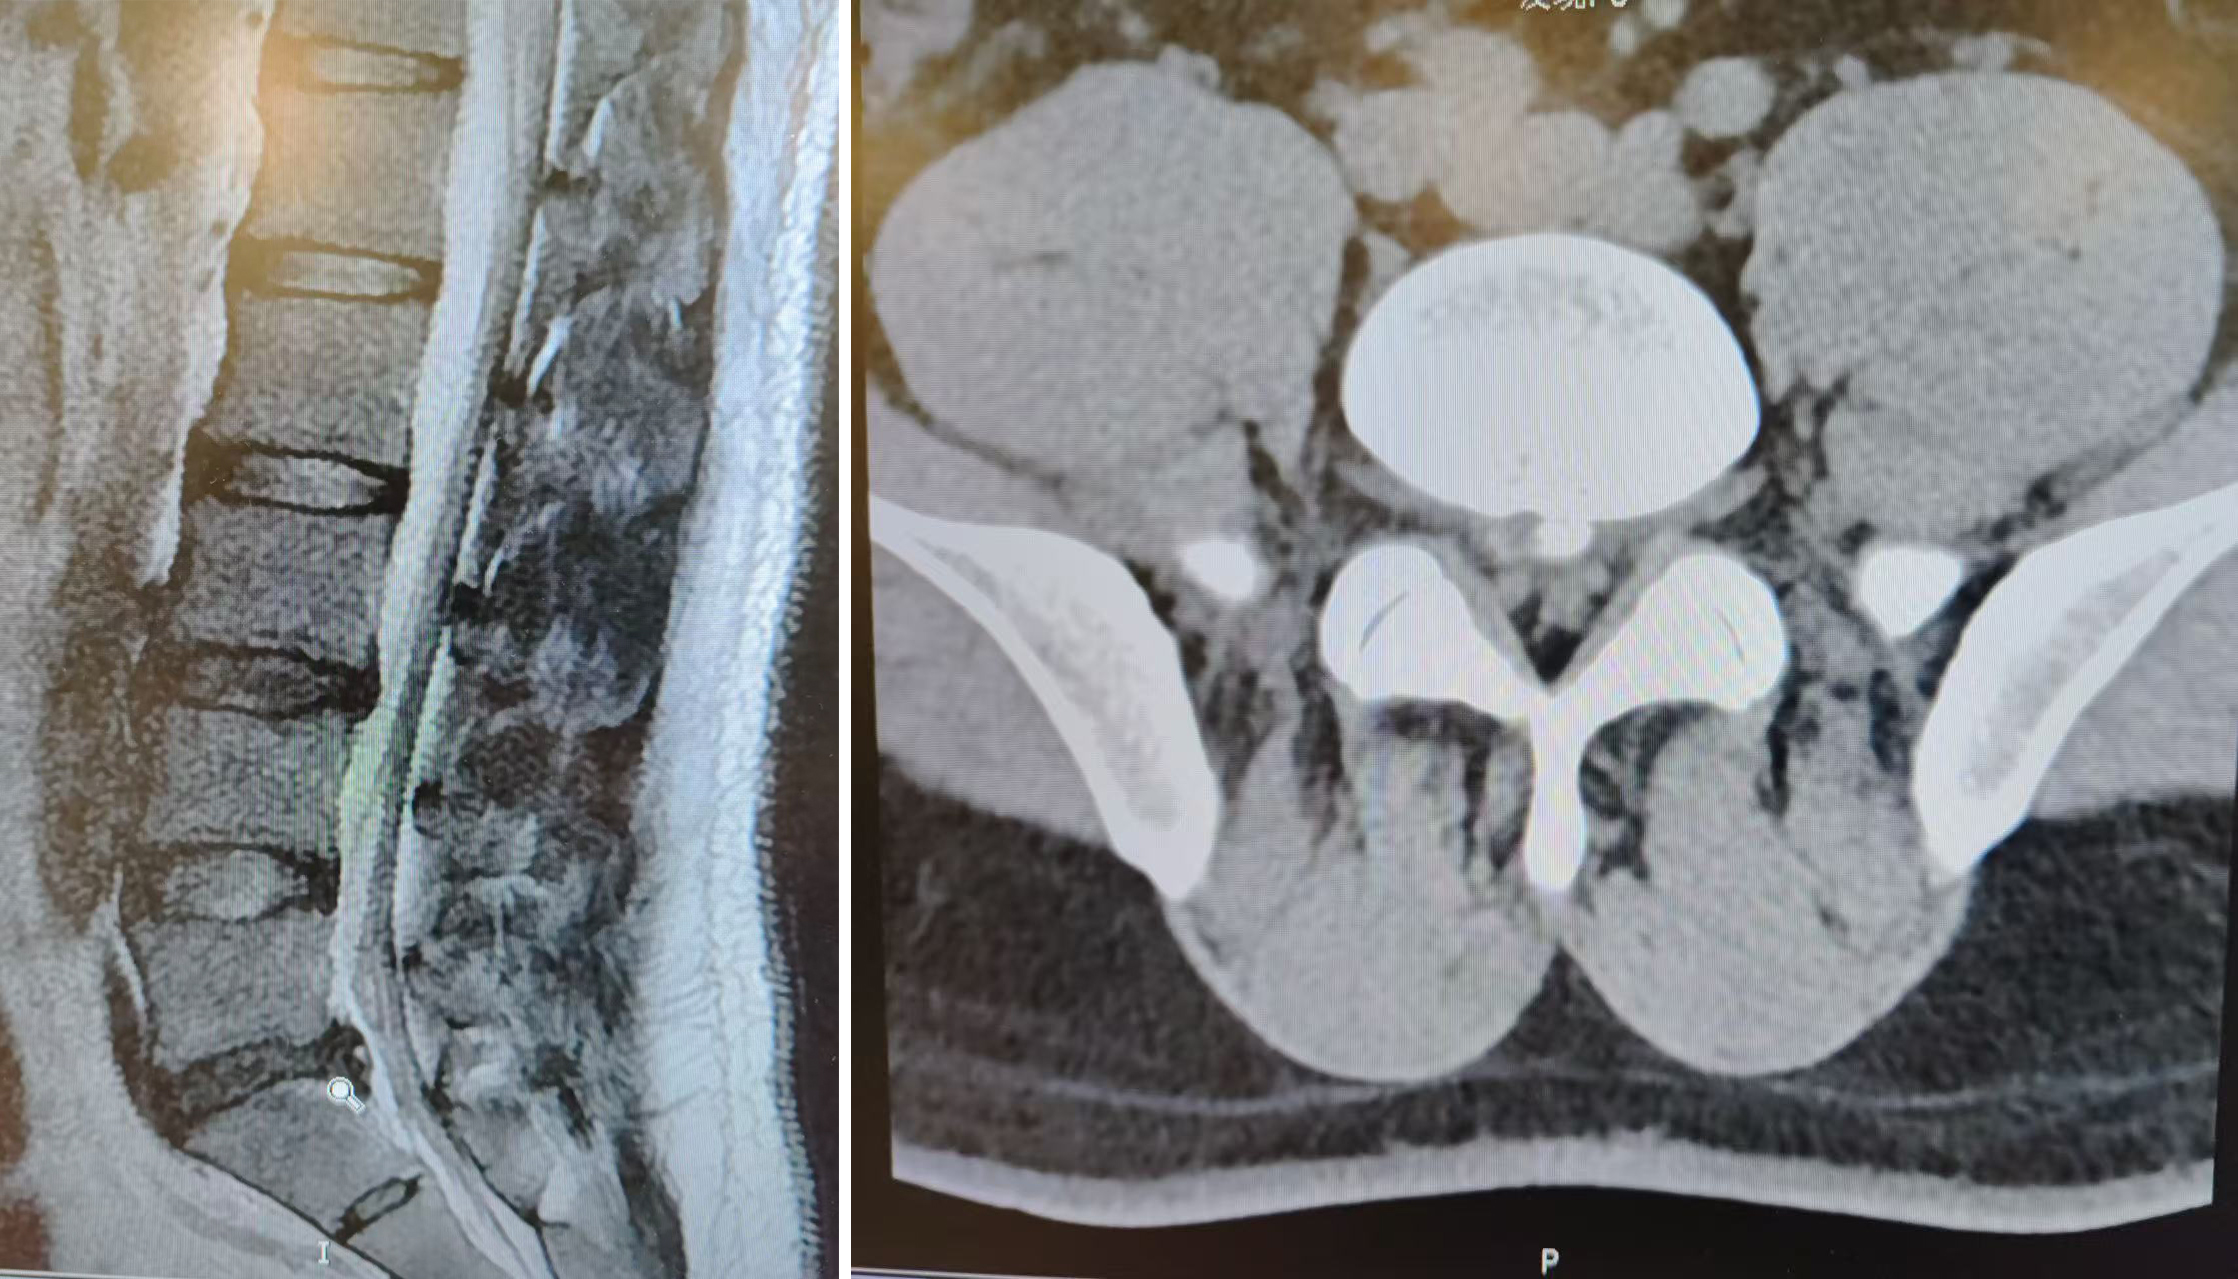

A patient presented with right lateral lower leg and lateral plantar pain and numbness, accompanied by low back pain, for one month. Symptoms were exacerbated by activity and only partially relieved at rest. Initial evaluation at an external clinic suggested lumbar spinal stenosis, prompting admission to our hospital. Imaging studies revealed straightening of lumbar lordosis, mild osteophyte formation, L3–L4 and L4–L5 disc bulges, and L5–S1 disc herniation. Thickening and calcification of the posterior longitudinal ligament resulted in secondary compression of the dural sac, correlating with the patient’s clinical symptoms.

After careful evaluation, Director Martin and Dr. Bingchen Dong of the Orthopedic Department determined that the patient would benefit from L5–S1 endoscopic foraminoplasty-assisted discectomy and annulus fibrosus repair. Intraoperatively, multiple nerve root variations were identified, significantly increasing surgical complexity and the risk of iatrogenic nerve injury. Leveraging extensive clinical experience and advanced technical skills, the surgical team successfully performed nucleus pulposus removal and annulus repair, achieving symptomatic relief, morphological restoration, and functional reconstruction simultaneously.